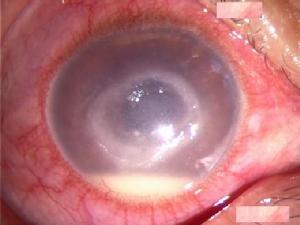

所有Behcet病患者中 有眼病變者約70%~85%。以眼病變為主要表現者,稱眼型Behcet病。眼病變中雖復發性前房積膿性虹膜睫狀體炎為經典表現,但以脈絡膜視網膜血管炎為主症者也並不少見,有時因眼球前段炎症而被忽略。

眼病變一般發生於其他器官炎症之後1、2年,也有首先出現者。因眼病就診的患者,除畏光、流淚、疼痛、視力下降等症狀外,尚有睫狀充血、灰白色KP;較稀薄的前房積膿,可隨體位轉變而緩慢改變其液平面,亦可在無睫狀充血等情況下突然出現 並能自發消失;虹膜後粘連、晶狀體瞳孔領被色素或滲出物遮蓋等體徵。少數病例還可見到虹膜角膜角的圓形黑色沉著物。如果眼底能窺見,則有玻璃體混濁,尤其下方灰白色疏鬆的團塊狀混濁;脈絡膜視網膜滲出、出血、視網膜血管充盈迂曲,甚至表現主幹或分支靜脈阻塞等;視盤充血水腫,邊緣出血等也時有發現。FFA可見廣泛的脈絡膜視網膜及視盤周圍螢光滲漏,也可因毛細血管阻塞而出現無灌注區,因FFA能誘發靜脈炎症反應,非不得已時儘量避免此項檢查。

1.眼部檢查 裂隙檢查可以發現特徵性的前房積膿,但出現率僅為40%,眼底鏡檢查可見下方玻璃體內雪球混濁,此體徵相對常見。